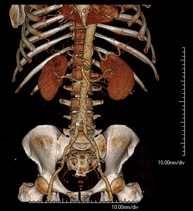

- Aortoiliac CT angiography

A non-invasive diagnostic test that involves examining the iliac arteries and abdominal aorta, obtaining high-definition anatomical images using CT (computed tomography) equipment and iodinated contrast dye. With the aid of workstations specialised for arterial studies, the image quality supports 2D and 3D reconstructions. This test is particularly recommended as a pre-surgical study (vascular map) prior to percutaneous or surgical interventions on the abdominal aorta, as a complementary study in patients with lower limb ischaemia, etc.